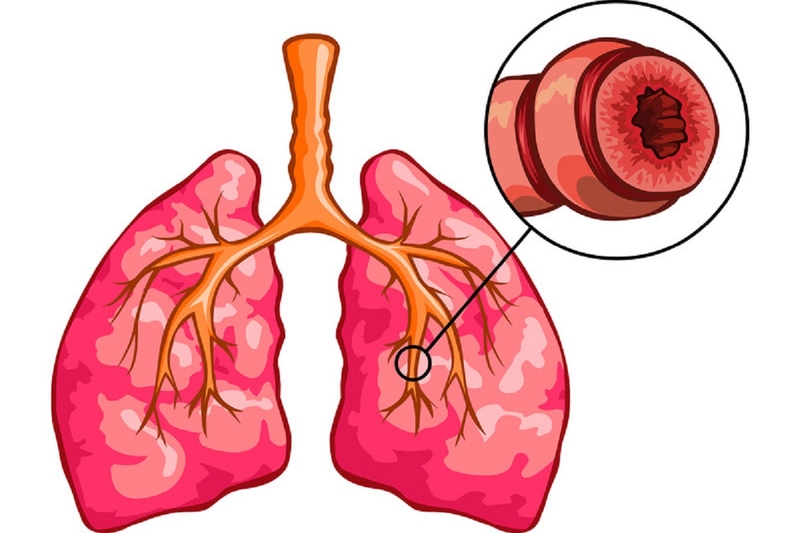

Viêm phế quản

Tùy vào tình trạng cấp tính hay mạn tính mà người bệnh có những triệu chứng khác nhau:

• Viêm phế quản cấp: Xảy ra cấp tính, kéo dài từ 2 - 3 tuần. Người bệnh có thể có sốt, ho, tức ngực, khạc đờm. Nghe phổi có ran rít, ran ngáy, ran ẩm. Khi khỏi bệnh hồi phục hoàn toàn và không để lại di chứng gì.

• Viêm phế quản mạn tính: Là bệnh lý tăng tiết nhầy cây phế quản, ho và khạc đờm xảy ra ít nhất 3 tháng/năm và ít nhất 2 năm liên tiếp, đã loại trừ lao và các bệnh lý tại phổi khác.

• Lâm sàng: Diễn biến từng đợt và nặng hơn vào mùa đông. Đợt bùng phát có thể có ho, sốt, khạc đờm mủ và khó thở. Có thể có triệu chứng của suy tim phải.

• Nghe phổi: Có ran rít, ran ngáy, ran ẩm tập trung ở nền phổi và rốn phổi.

• X quang: Có hình ảnh phổi bẩn.

• Đo chức năng hô hấp: Có thể có rối loạn thông khí tắc nghẽn hay rối loạn thông khí hỗn hợp không hồi phục.

Hội chứng phế quản là gì? Nguyên nhân và triệu chứng thường gặp trong hội chứng phế quản Viêm phế quản là một nguyên nhân thường gặp nhất gây hội chứng phế quản